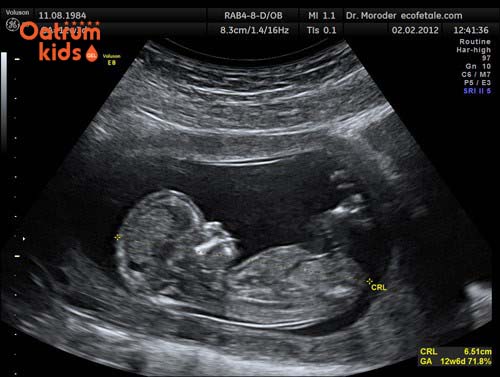

Bình thường từ tuần thứ 4 của thai kỳ thì mũi của trẻ đã bắt đầu hình thành, nó giống như một phần đường thở quan trọng của bào thai. Đến khoảng tuần thai thứ 11 các thành phần cơ bản của mũi cũng đã được hình thành, do đó ở thời điểm này các mẹ cần đến ngay bệnh viện để siêu âm kiểm tra xem chiều dài xương mũi thai nhi chuẩn hay chưa.

Đo chiều dài xương mũi thai nhi thường được bác sỹ chỉ định vào tuần thứ 17, 18, 21, 23, 25 hay 27 hoặc 3 tháng giữa thai kỳ. Cũng theo các chuyên gia y tế thì chiều dài xương mũi bao nhiêu, dài hay ngắn còn tùy thuộc vào di truyền, dân tộc cũng như độ tuổi thai.